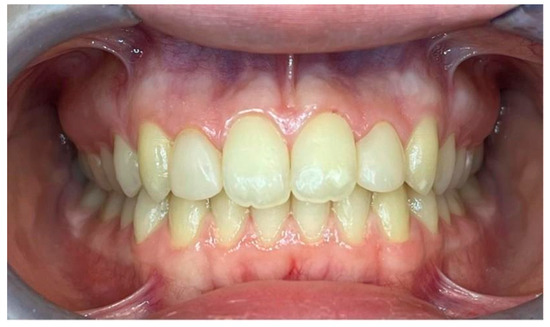

2.1. Case 1

2.1.5. Therapeutic Intervention

2.2. Case 2

2.2.5. Therapeutic Intervention